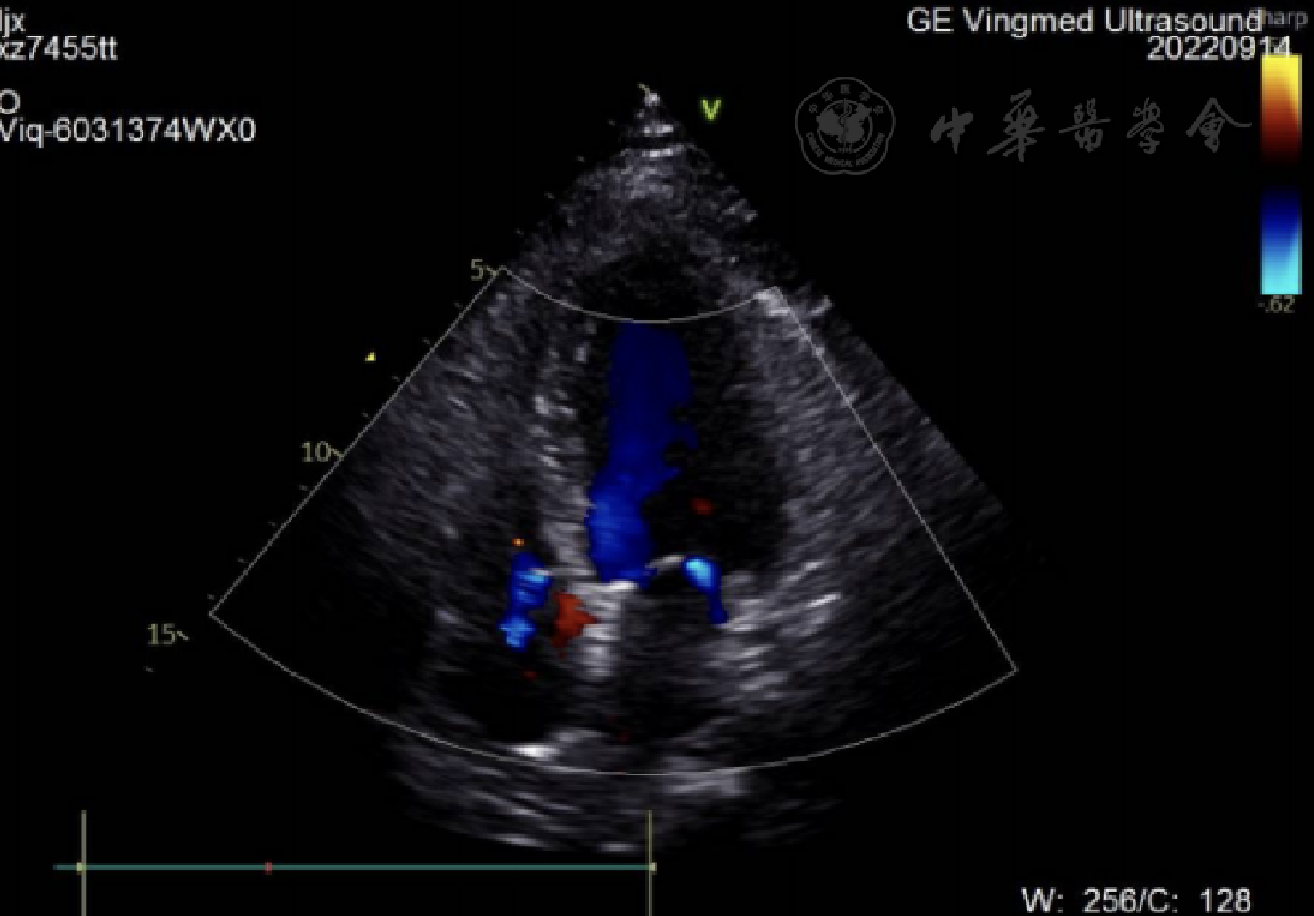

入院后行急诊冠脉造影术,结果见图1。行心脏彩超和心电图检查,结果见图2,图3。

图2 心脏彩超结果

LVD 42 mm,EF 42%,轻度二尖瓣反流;轻度三尖瓣反流,左室壁整体运动幅度普遍减低。